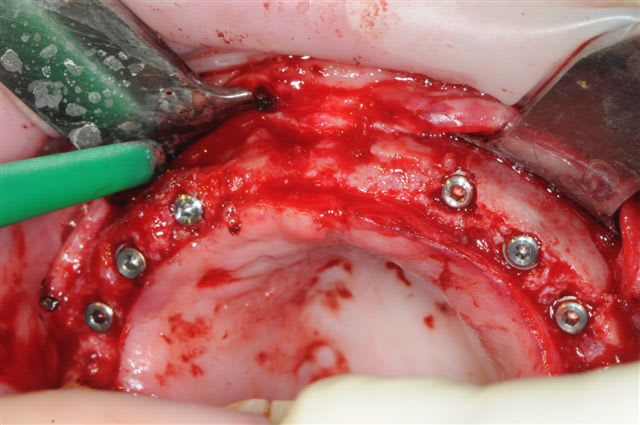

Yes, ça c'est fait!

merci à D57 qui m'a soutenu moralement.

je peux enfin confirmer que la greffe biobank, autorise l'expansion en deuxième intention.

même si je n'ai pas fait un super bombé vestibulaire je me suis permis de faire un mini expansion de crête en particulier sur 22

os magnifiquement vascularisé! excellente adhérence du greffon.

l'expansion, à bien faillit mal tourner à cause d'un expanseur qui a tourné à 40.000tr/min au lieu de 40tr/min. l'a eut chaud le pxav!

pas 40000, mais 2000 t/mn, ce qui n'est pas un bon plan pour les expanseurs meissinger, et à je crois bien provoqué un "m...e!" violent et la peur d'avoir tout explosé.

Mais non, mis à part une pénétration profonde (le spreader fait 15 mm pour une prévision d'implant de 10 mm)pas d'autres conséquence que des micros fractures crestale.

Concernant la résorption du greffon, même constatations que Growler: aucune, les seuls zones qui ont fait reculer la date d'intervention, de 2 mois sont des zones de jonction avec l'os du patient qui avait du mal à fusionner car trop fin au départ (moins d'un mm)je pense.

Pour Posit, l'expansion c'était ma cerise sur le gâteau, et ma façon de prouver que le greffon était parfaitement "vivant" ou au moins travaillable.

l'expansion en 22 à la jonction greffon os propre, faite à l'ostéotome manuel, malgré la non approbation de Thomas, c'est parfaitement passée, et nous avons constatés la parfaite liaison du bloc.